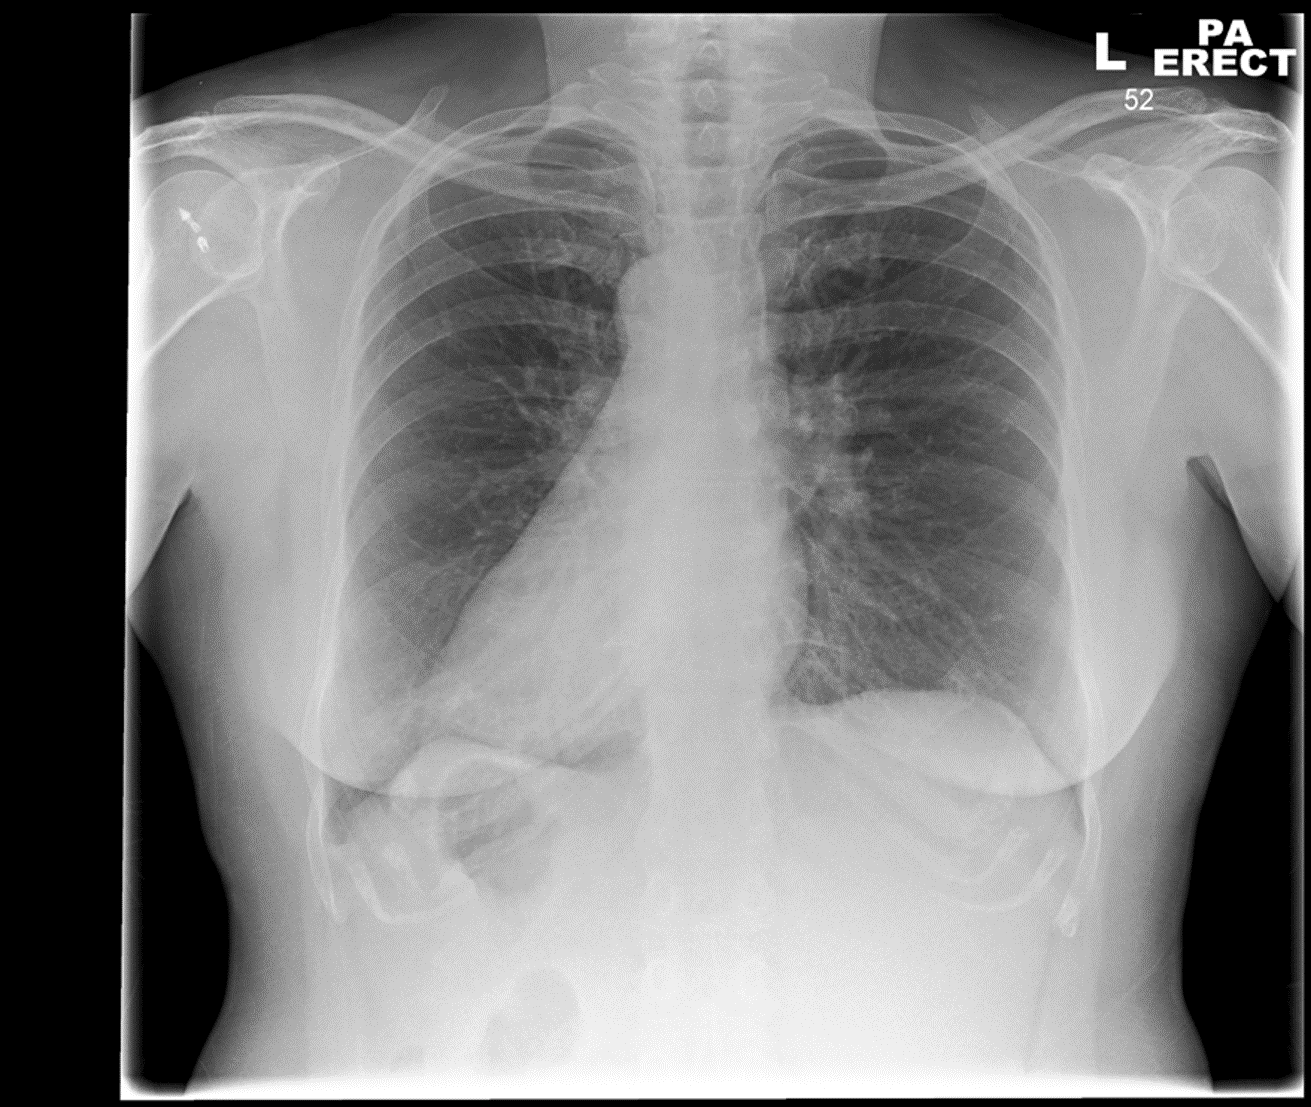

Dull ache on the right side. ?cause

• Right-sided (1)

• Pneumothorax in the apex of the right lung (1)

• The left side is normal (1)